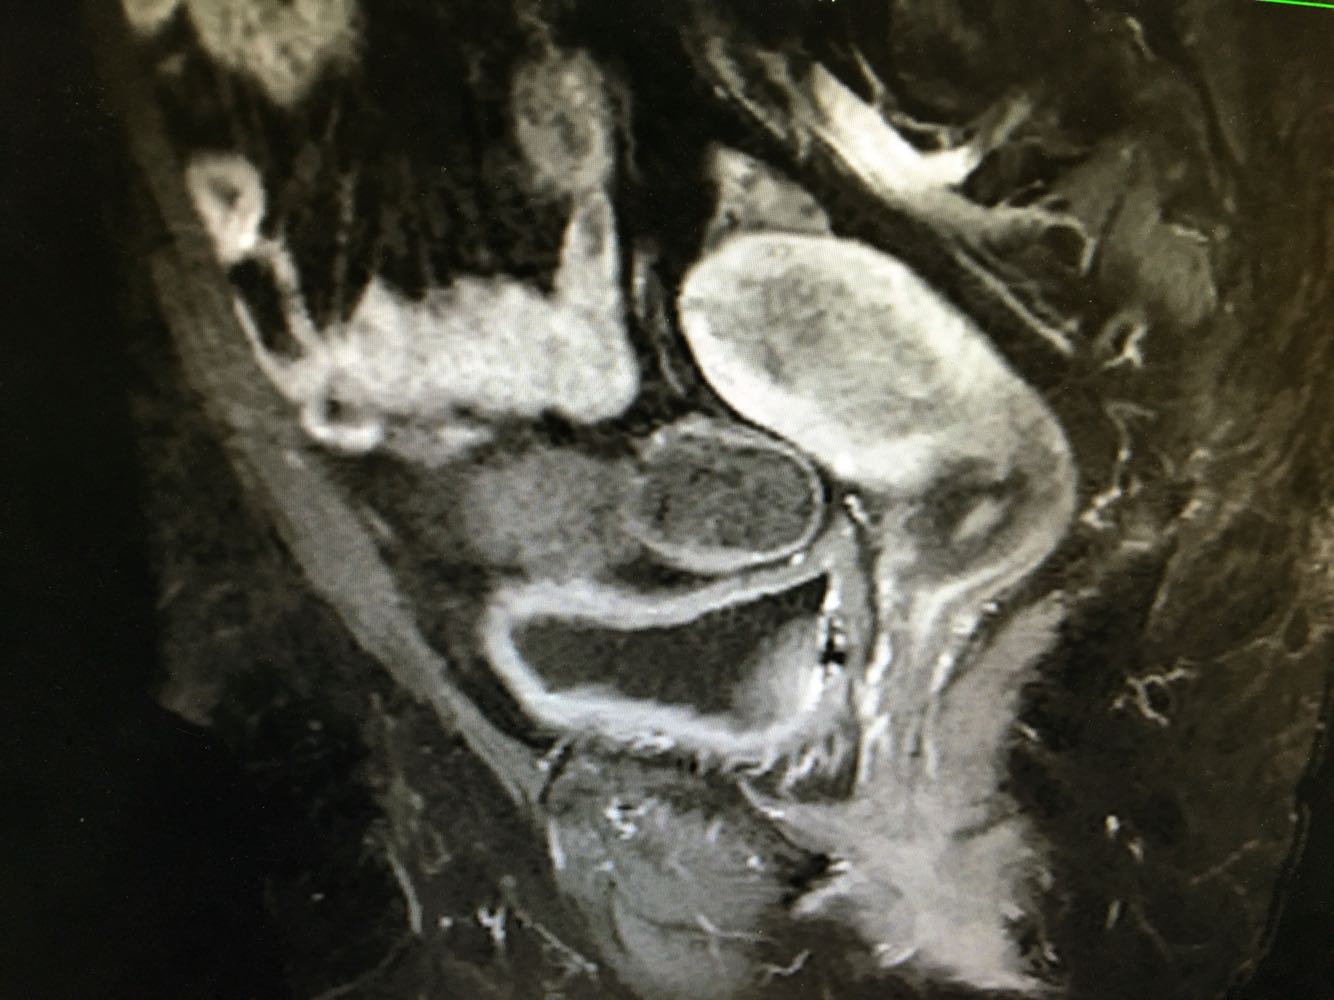

妇科检查:  妇科检查: 外阴(-);阴道畅,少量血性分泌物;宫颈轻糜,无活动性出血;宫体中位,常大,质中,无压痛;附件未及异常,无压痛。 辅助检查:我院 【ECG】ST段改变。    【妇科B超】内膜双侧厚:16,回声不均匀,内引出血流信号,与周围肌层分界不清。诊断意见:子宫内膜增厚,回声不均匀,Ca待查,请结合临床。

诊断:绝经后出血 诊疗方案:患者入院后完善各项检查排除手术禁忌症,行B超下分段诊刮术,刮勺搔刮宫颈管极少量组织刮出,并涂片送检脱落细胞。 探宫腔深6.5cm,刮勺搔刮宫腔四周2圈,感宫壁滑腻,刮出少量鱼肉样组织,送病理, 同时涂片送检脱落细胞 ,手术顺利。